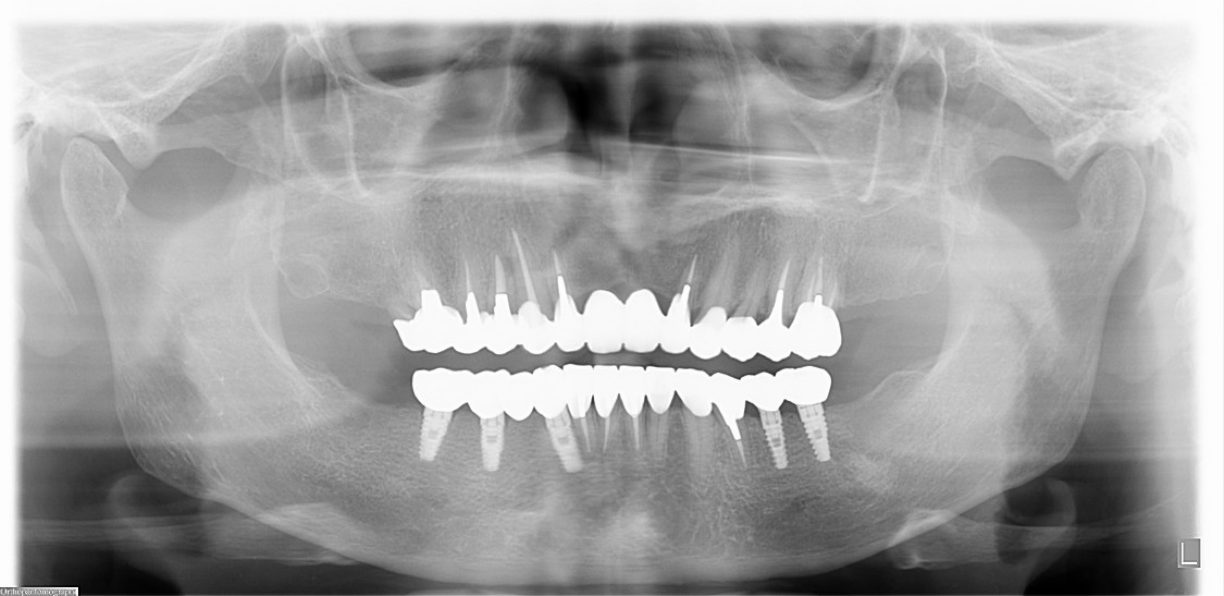

| 主訴 | 全顎治療希望、歯が無いので噛みずらい。定年で時間の余裕出来たので、インプラントで治療して欲しい。 |

| 治療内容 | プラークコントロール不良なため歯周治療を行い、残存歯を極力温存し、欠損部インプラントを施し咬合再構成を行う。 プロビジョナルレストレーションによる咬合関係を模索した後、全顎にわたりセラミックによる補綴治療、その後メインテナンスに移行 |

| 治療費 | 6,470,000円(税込)(インプラントすべて含む) |

| 治療期間 | 1年6ヶ月 |

| 治療回数 | 72回 |

| 想定されたリスク | 食いしばり(パラファンクション)によるセラミックの破折、歯の破折 |